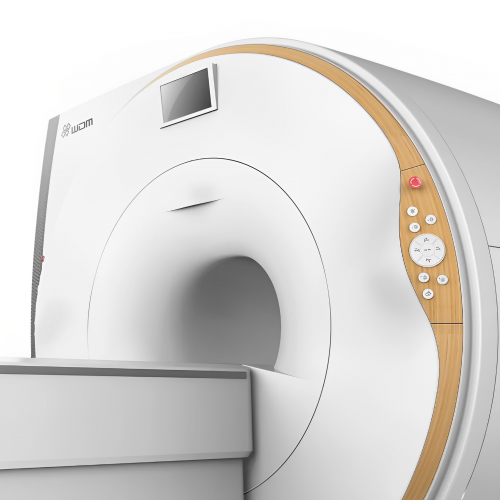

RF optical technology significantly increases the SNR coefficient and image quality

Ultrashort hole with a spacious hole diameter

8-32 channels of parallel registration to achieve higher scanning speed

Zero helium consumption technology

Mobile device management is available